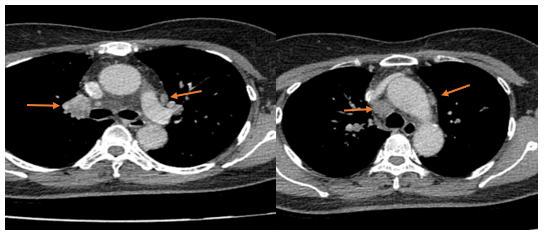

- Chụp cắt lớp vi tính lồng ngực: Nhu mô thùy trên phổi (Phải) có nốt tổn thương kích thước 13x14mm,bờ không đều, ngấm thuốc, sau tiêm. Rải rác nốt đặc 2 bên thùy phổi kích thước 3-10mm. Trung thất các nhóm 1R; 2R; 4R; 5; 8; 10RL có vài hạch lớn nhất kích thước 26x15mm; bờ không đều; ngấm thuốc không đồng nhất sau tiêm. Thượng đòn 2 bên có vài hạch tính chất tương tự; hạch bên phải kích thước 11x14mm

Hình 1.

Hình ảnh cắt lớp vi tính ngực có tiêm: thùy trên phổi (P) có nốt tổn thương kích thước 13x14mm, bờ không đều, ngấm thuốc, sau tiêm. Nghi ngờ tổn thương nguyên phát (mũi tên đỏ)

Hình 2: Hình ảnh cắt lớp vi tính ngực có tiêm: Rải rác nốt đặc 2 bên thùy phổi kích thước 3-10mm (các mũi tên màu xanh lá)

Hình 3: Hình ảnh cắt lớp vi tính ngực có tiêm: Trung thất các nhóm 1R; 2R; 4R; 5; 8; 10RL có vài hạch lớn nhất kích thước 26x15mm; bờ không đều; ngấm thuốc không đồng nhất sau tiêm (mũi tên màu cam)